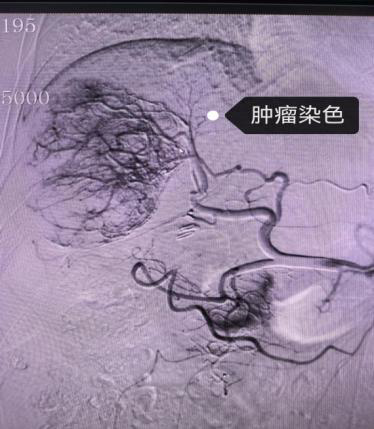

(二)肿瘤治疗

在肿瘤治疗领域,介入同样表现非凡。它可以将化疗药物直接输送到肿瘤部位,提高局部药物浓度,增强治疗效果,同时减少对全身的副作用。又或是通过血管栓塞,切断肿瘤的营养供应,抑制肿瘤生长,为患者带来新的希望。

肝Ca介入治疗